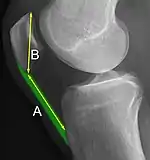

Insall-Salvati ratio (A divided by B).[6]

The Insall-Salvati ratio helps to indicate patella baja on lateral X-rays, and is calculated as the patellar tendon length divided by the patellar bone length. An Insall-Salvati ratio of < 0.8 indicates patella baja.[6]